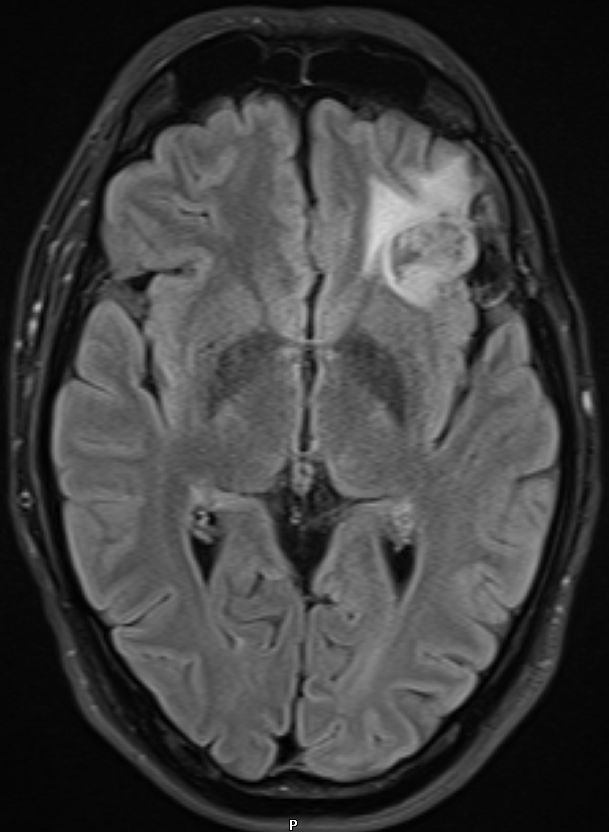

| Kasuistik 2 | Astrozytom Grad 2 li. frontal | 32 jährigen schlanken sportlicher Mann. Nie ernsthaft krank gewesen. | 6 Monaten vorher eine Phase der Orientierungslosigkeit. Dann generalisierter Krampfanfall mit Bewusstseinsverlust. | Therapie: Tumorresektion, postoperative Bestrahlung mit 50Gy. |

4 Jahre nach Primärtherapie asymptomatischer Tumor in der MRT-Kontrolle.![]() |

![]() Histologie: Glioblastoma multiforme | |||